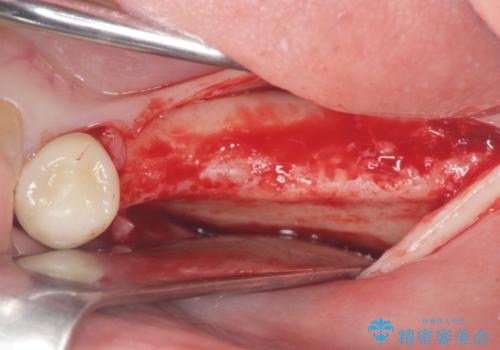

骨の量が比較的十分に保たれていたため、インプラントを埋入し1ヶ月後には仮歯を入れてしっかりと咬合機能を回復することができました。

- 外科手術のため、術後に痛みや腫れ、違和感を伴います